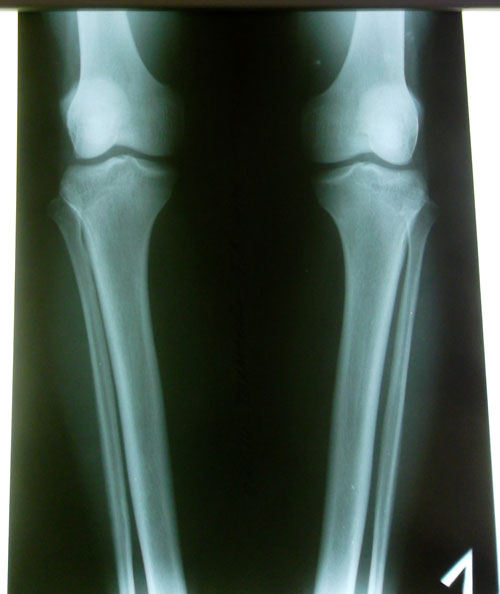

Диагноз: О - образная деформация ног

Исходник

Дата операции 29.01.2014г.

рентген до операции